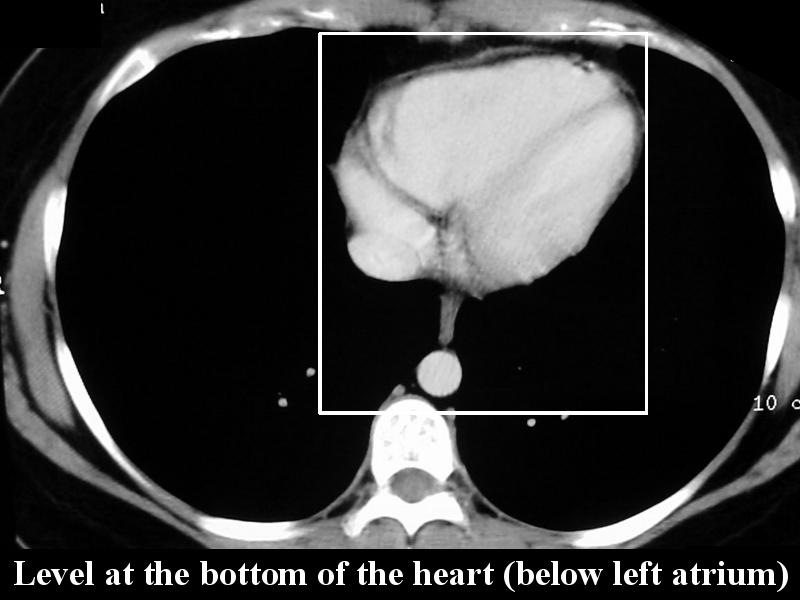

MS 156 CT 74